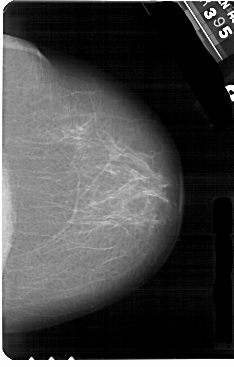

A_1266_1.LEFT_MLO

ics_version 1.0

filename A-1266-1

DATE_OF_STUDY 3 3 1995

PATIENT_AGE 67

FILM_TYPE REGULAR

DENSITY 2

DATE_DIGITIZED 17 7 1998

DIGITIZER HOWTEK 43.5

LEFT_MLO LINES 5491 PIXELS_PER_LINE 3586 BITS_PER_PIXEL 12 RESOLUTION 43.5 OVERLAY